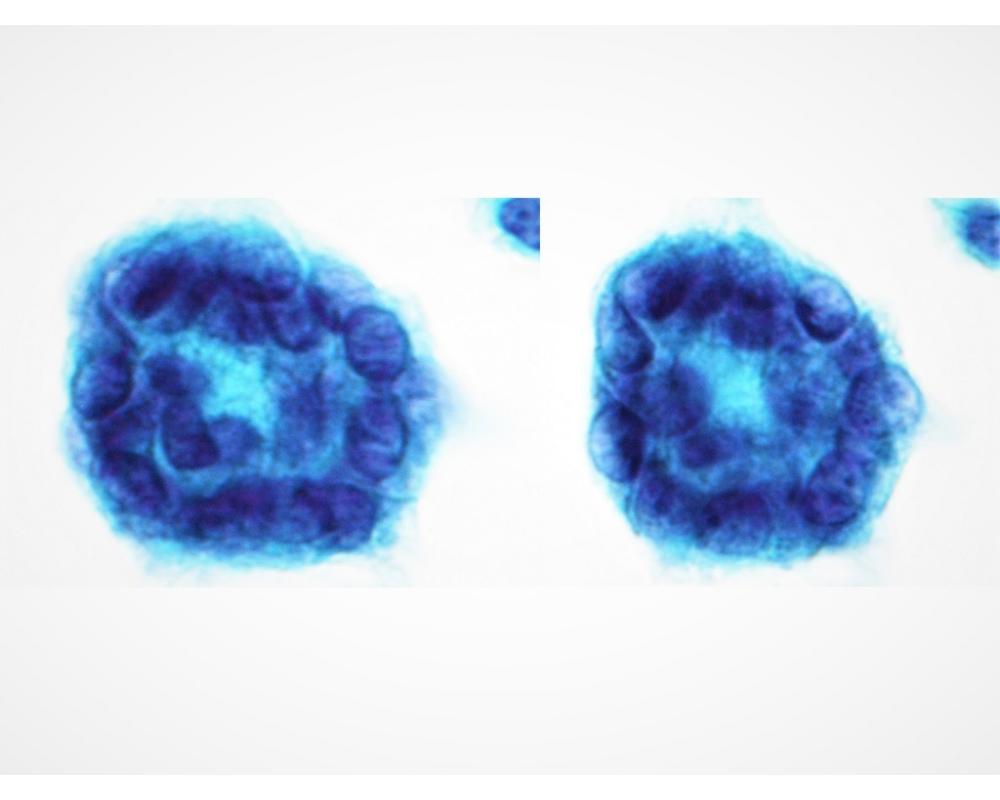

種別:体腔液

| 年齢 | 50代 | 性別 | 女性 |

| 採取部位 | 胸水 | 採取方法 | 穿刺 |

既往歴:10年以上前に、腹部腫瘍の手術歴がある。

現病歴:X-10年に、胸水貯留の精査過程で腫瘍が認められ、現在まで化学療法を継続中である。直近の、胸水穿

刺吸引検体より作製された標本を提示する。

| 正解 | 5.高分化乳頭状中皮腫 |